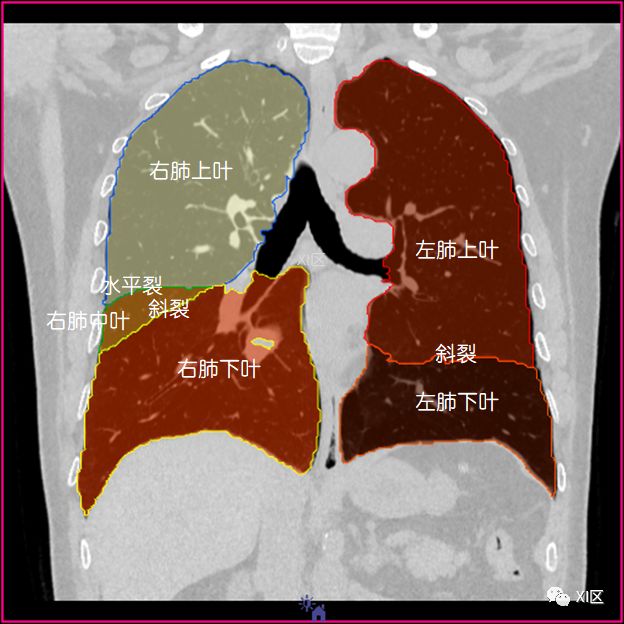

肺的分叶

左肺借斜裂成上、下两叶;右肺借斜裂和水平裂成上、中和下叶三叶。

冠状位